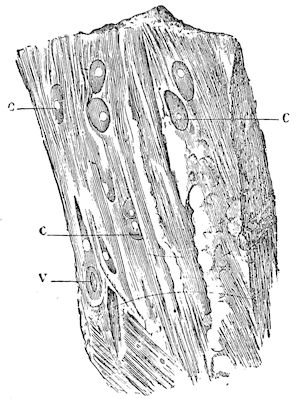

Fig. 8.—Transverse section through the middle region of the face in a pig suffering from osseous cachexia.

The fractures which occur so frequently during the osteoclastic phase have well-marked peculiarities. The extravasation of blood is trifling, and no callus forms, even when the ends of the bones are immobilised by external aid; if the ends are left free, they soon become worn and polished by rubbing against one another.

In the neighbourhood of the articulations and ligamentous insertions the periosteum soon undergoes change, and it is not uncommon to find sub-periosteal and intra-osseous extravasations of blood.

Germain has also noted in horses the disappearance of the intervertebral and articular cartilages, and the frequent occurrence of anchylosis, true or false.

18In the final stages, the bones may be cut with a knife, and a time arrives when bony tissue seems completely to have disappeared; thus, as shown in Fig. 8 herewith, it was possible to cut the entire head of a pig into thin slices without the slightest difficulty. All parts of the head had been affected by the softening change.

From the chemical point of view, the diminution in mineral salts and in phosphate of calcium has long been recognised, but the degree of this change varies according to the phase. In human beings the proportions have been estimated as follows: Normal bone, 50 to 80 per cent. of phosphate of calcium; bone in persons suffering from osteomalacia, 5 to 20 per cent. of phosphate of calcium. The changes in the ossein have not been carefully studied. We only know that histologically the ossein becomes fibrillar, and that chemically it no longer retains its normal composition.